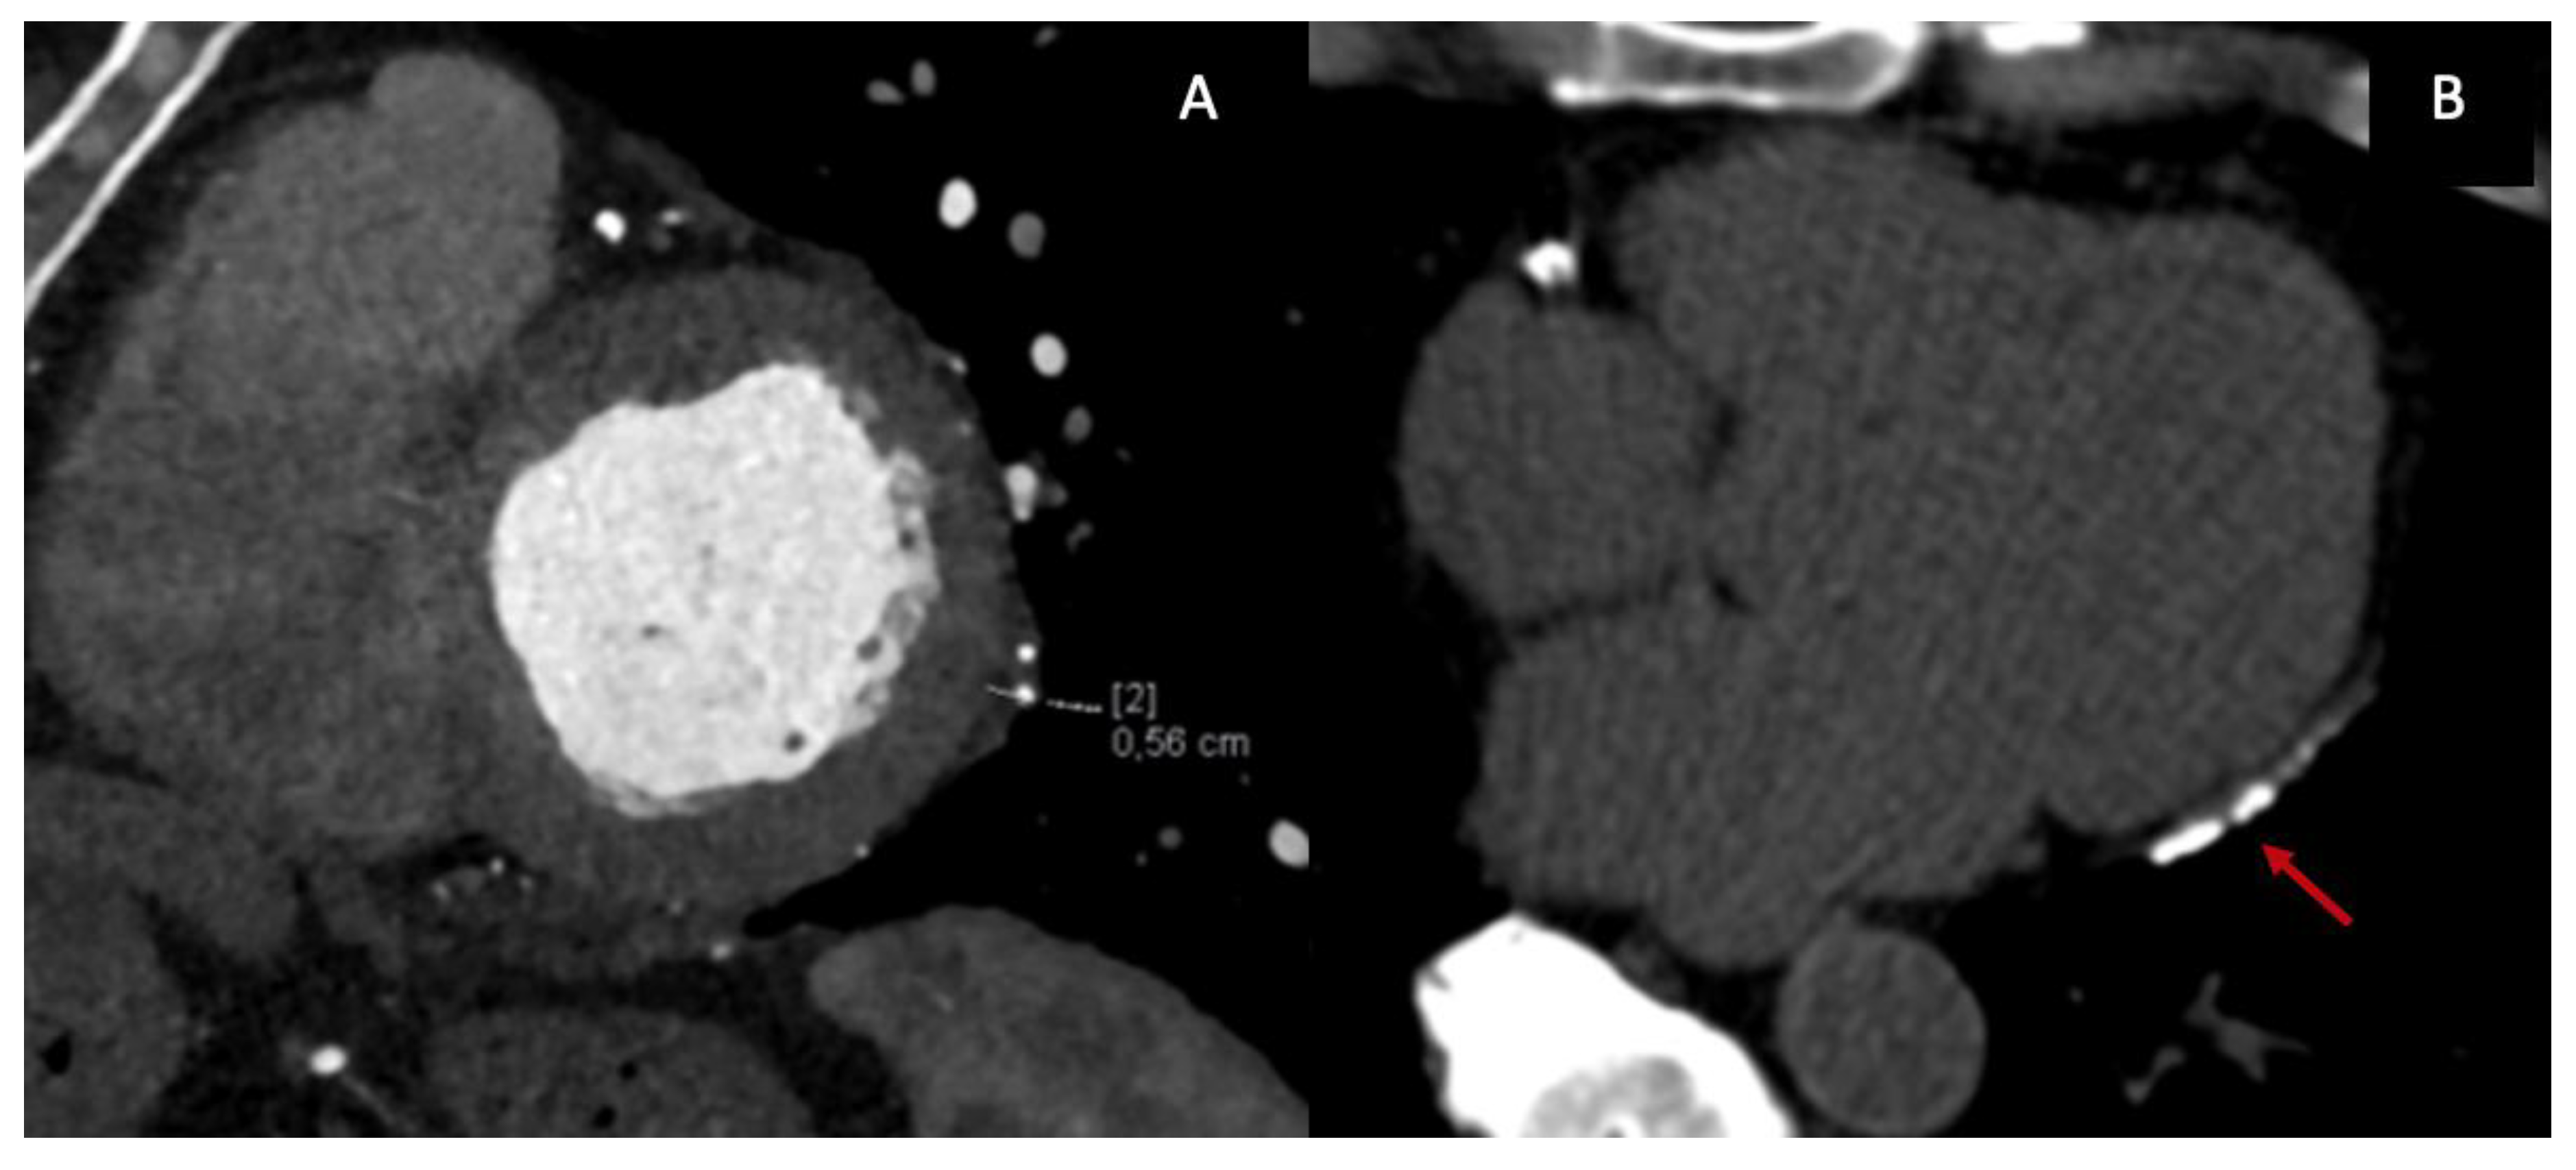

Anatomical assessment begins with black-blood spin-echo sequences, which allow evaluation of pericardial anatomy and thickness, and cine steady-state free-precession (SSFP) sequences, which provide detailed visualization of pericardial morphology and ventricular interaction. Cine imaging depicts classical features of CP, including tubular or conical ventricular geometry, impaired diastolic expansion, exaggerated ventricular interdependence, and the early-diastolic septal “bounce”. Although pericardial thickening >4 mm is traditionally considered suggestive of CP, thickness alone is an unreliable discriminator: many patients with established constriction, particularly those with early inflammatory disease or postsurgical adhesions, exhibit normal pericardial thickness [21]. Current recommendations, therefore, emphasize the integration of anatomic, functional, and tissue-based parameters rather than relying on thickness in isolation. Furthermore, CMR allows direct visualization of constrictive physiology through real-time free-breathing cine imaging, which captures exaggerated ventricular interdependence and respiratory-induced septal shift (Figure 2.A).

LGE provides complementary information on inflammatory activity and fibrosis and is central to defining the chronicity of disease (Figure 2.B).

Figure 2. CMR findings in CP: real-time free-breathing cine imaging shows respiratory-induced septal shift (A) (red arrow); pericardial LGE (B) (yellow arrow).